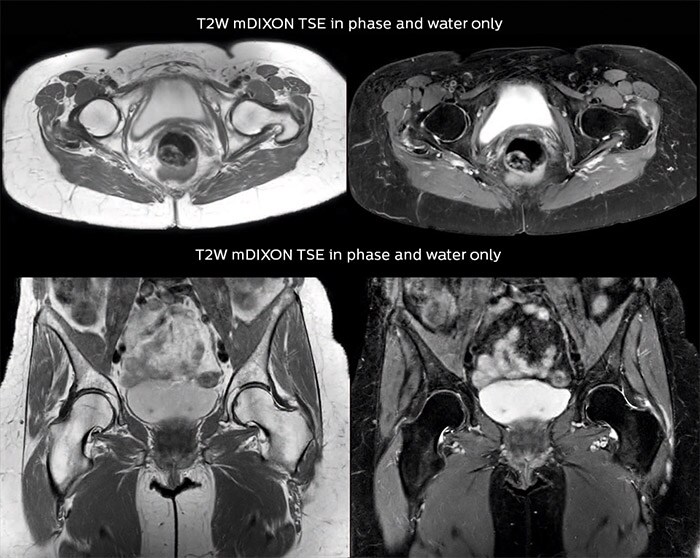

“При визуализации периферических суставов режим mDIXON TSE помогает диагностировать травмы связок или сухожилий, дегенеративные и воспалительные патологии, такие как остеоартрит и ревматологические заболевания, а также злокачественные новообразования.” “При оценке сухожилий и связок вокруг колена, голени, таза и локтя режим mDIXON TSE обусловливает достоверность диагностики благодаря способности получения изображений с подавлением и без подавления сигнала жира без дополнительных затрат времени. Это стало возможным в связи с тем, что сканирование в 2-точечном режиме mDIXON выполняется быстрее, чем с помощью обычного 3-точечного метода Dixon. Он может обладать более высокой эффективностью, поскольку помогает избежать увеличения продолжительности сканирования.” “mDIXON TSE sequences allow simultaneous characterization of morphological changes from the in-phase T2-weighted images and visualization of edematous changes, thanks to the water T2-weighted images from the same acquisition. Anatomical and morphological considerations could be a partial or complete ligament tear, a bony avulsion or hematoma.” “For soft tissue assessment mDIXON brings similar benefits. For example in one T2-weighted mDIXON TSE acquisition, having the multiple contrasts helps us assess abnormalities in peripheral nerves fascicles, which may be due to anatomical or inflammatory changes..” “In peripheral joints, we get good image quality in difficult areas with mDIXON TSE. Fat suppressed images appear homogeneous over the entire image, even with large coverage at 3.0T – for instance in scapular or hip girdles – or in the bearing areas or around metal prostheses*, where fat suppression is often deficient with STIR or spectral fat suppression, causing diagnostic difficulties. If a diagnostic image is right the first time, we don’t need to repeat or add a sequence.” “mDIXON TSE sequences allow simultaneous characterization of morphological changes from the in-phase T2-weighted images and visualization of edematous changes, thanks to the water T2-weighted images from the same acquisition. Anatomical and morphological considerations could be a partial or complete ligament tear, a bony avulsion or hematoma.” “For soft tissue assessment mDIXON brings similar benefits. For example in one T2-weighted mDIXON TSE acquisition, having the multiple contrasts helps us assess abnormalities in peripheral nerves fascicles, which may be due to anatomical or inflammatory changes..”

“С помощью режима mDIXON TSE мы получаем изображения периферических суставов хорошего качества, даже на сложных участках.

Сигнал от жира подавляется однородно по всему изображению, даже в исследованиях с большим охватом при 3,0 Тл, например в исследованиях лопаток, тазового пояса, опорных поверхностей или тканей вокруг металлических протезов*, где технология STIR или функция спектрального подавления жира не обеспечивают необходимого уровня подавления. Если удается с первого раза получить нужное диагностическое изображение, нам не придется повторять сканирование или добавлять последовательность.” “Последовательности mDIXON TSE позволяют одновременно диагностировать анатомические изменения по синфазным T2-взвешенным изображениям и визуализировать отечные изменения благодаря T2-взвешенным изображениям воды, полученным в ходе того же сканирования. Возможные анатомические заключения: частичный или полный разрыв связки, авульсия кости или гематомa.” “При оценке мягких тканей режим mDIXON дает аналогичные преимущества. Например, всего одно сканирование с T2-взвешенной последовательностью mDIXON TSE, позволяющей получить несколько типов контраста, помогает оценить аномалии пучков периферических нервов, которые могут быть обусловлены анатомическими изменениями или воспалением.” “mDIXON TSE sequences allow simultaneous characterization of morphological changes from the in-phase T2-weighted images and visualization of edematous changes, thanks to the water T2-weighted images from the same acquisition. Anatomical and morphological considerations could be a partial or complete ligament tear, a bony avulsion or hematoma.” “For soft tissue assessment mDIXON brings similar benefits. For example in one T2-weighted mDIXON TSE acquisition, having the multiple contrasts helps us assess abnormalities in peripheral nerves fascicles, which may be due to anatomical or inflammatory changes..” “In peripheral joints, we get good image quality in difficult areas with mDIXON TSE. Fat suppressed images appear homogeneous over the entire image, even with large coverage at 3.0T – for instance in scapular or hip girdles – or in the bearing areas or around metal prostheses*, where fat suppression is often deficient with STIR or spectral fat suppression, causing diagnostic difficulties. If a diagnostic image is right the first time, we don’t need to repeat or add a sequence.” “mDIXON TSE sequences allow simultaneous characterization of morphological changes from the in-phase T2-weighted images and visualization of edematous changes, thanks to the water T2-weighted images from the same acquisition. Anatomical and morphological considerations could be a partial or complete ligament tear, a bony avulsion or hematoma.” “For soft tissue assessment mDIXON brings similar benefits. For example in one T2-weighted mDIXON TSE acquisition, having the multiple contrasts helps us assess abnormalities in peripheral nerves fascicles, which may be due to anatomical or inflammatory changes..”